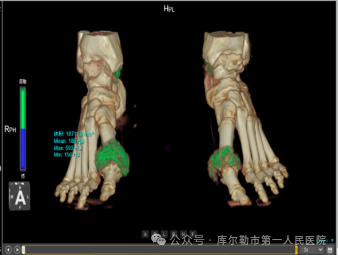

5、功能成像方案

能谱成像技术:分析人体病灶的组织成分、组织特性,为影像诊断提供常规CT无法提供的重要信息,如进行痛风石检测、泌尿系结石成分分析、碘与钙质区分、肿瘤同源性鉴别等。

▲ 痛风石检测

▲ 泌尿系结石分析医院仪器怎么成像【医院动态】库尔勒市第一人民医院医学影像科引进新设备,助推医院高质量发展_https://www.jmylbn.com_新闻资讯_第21张